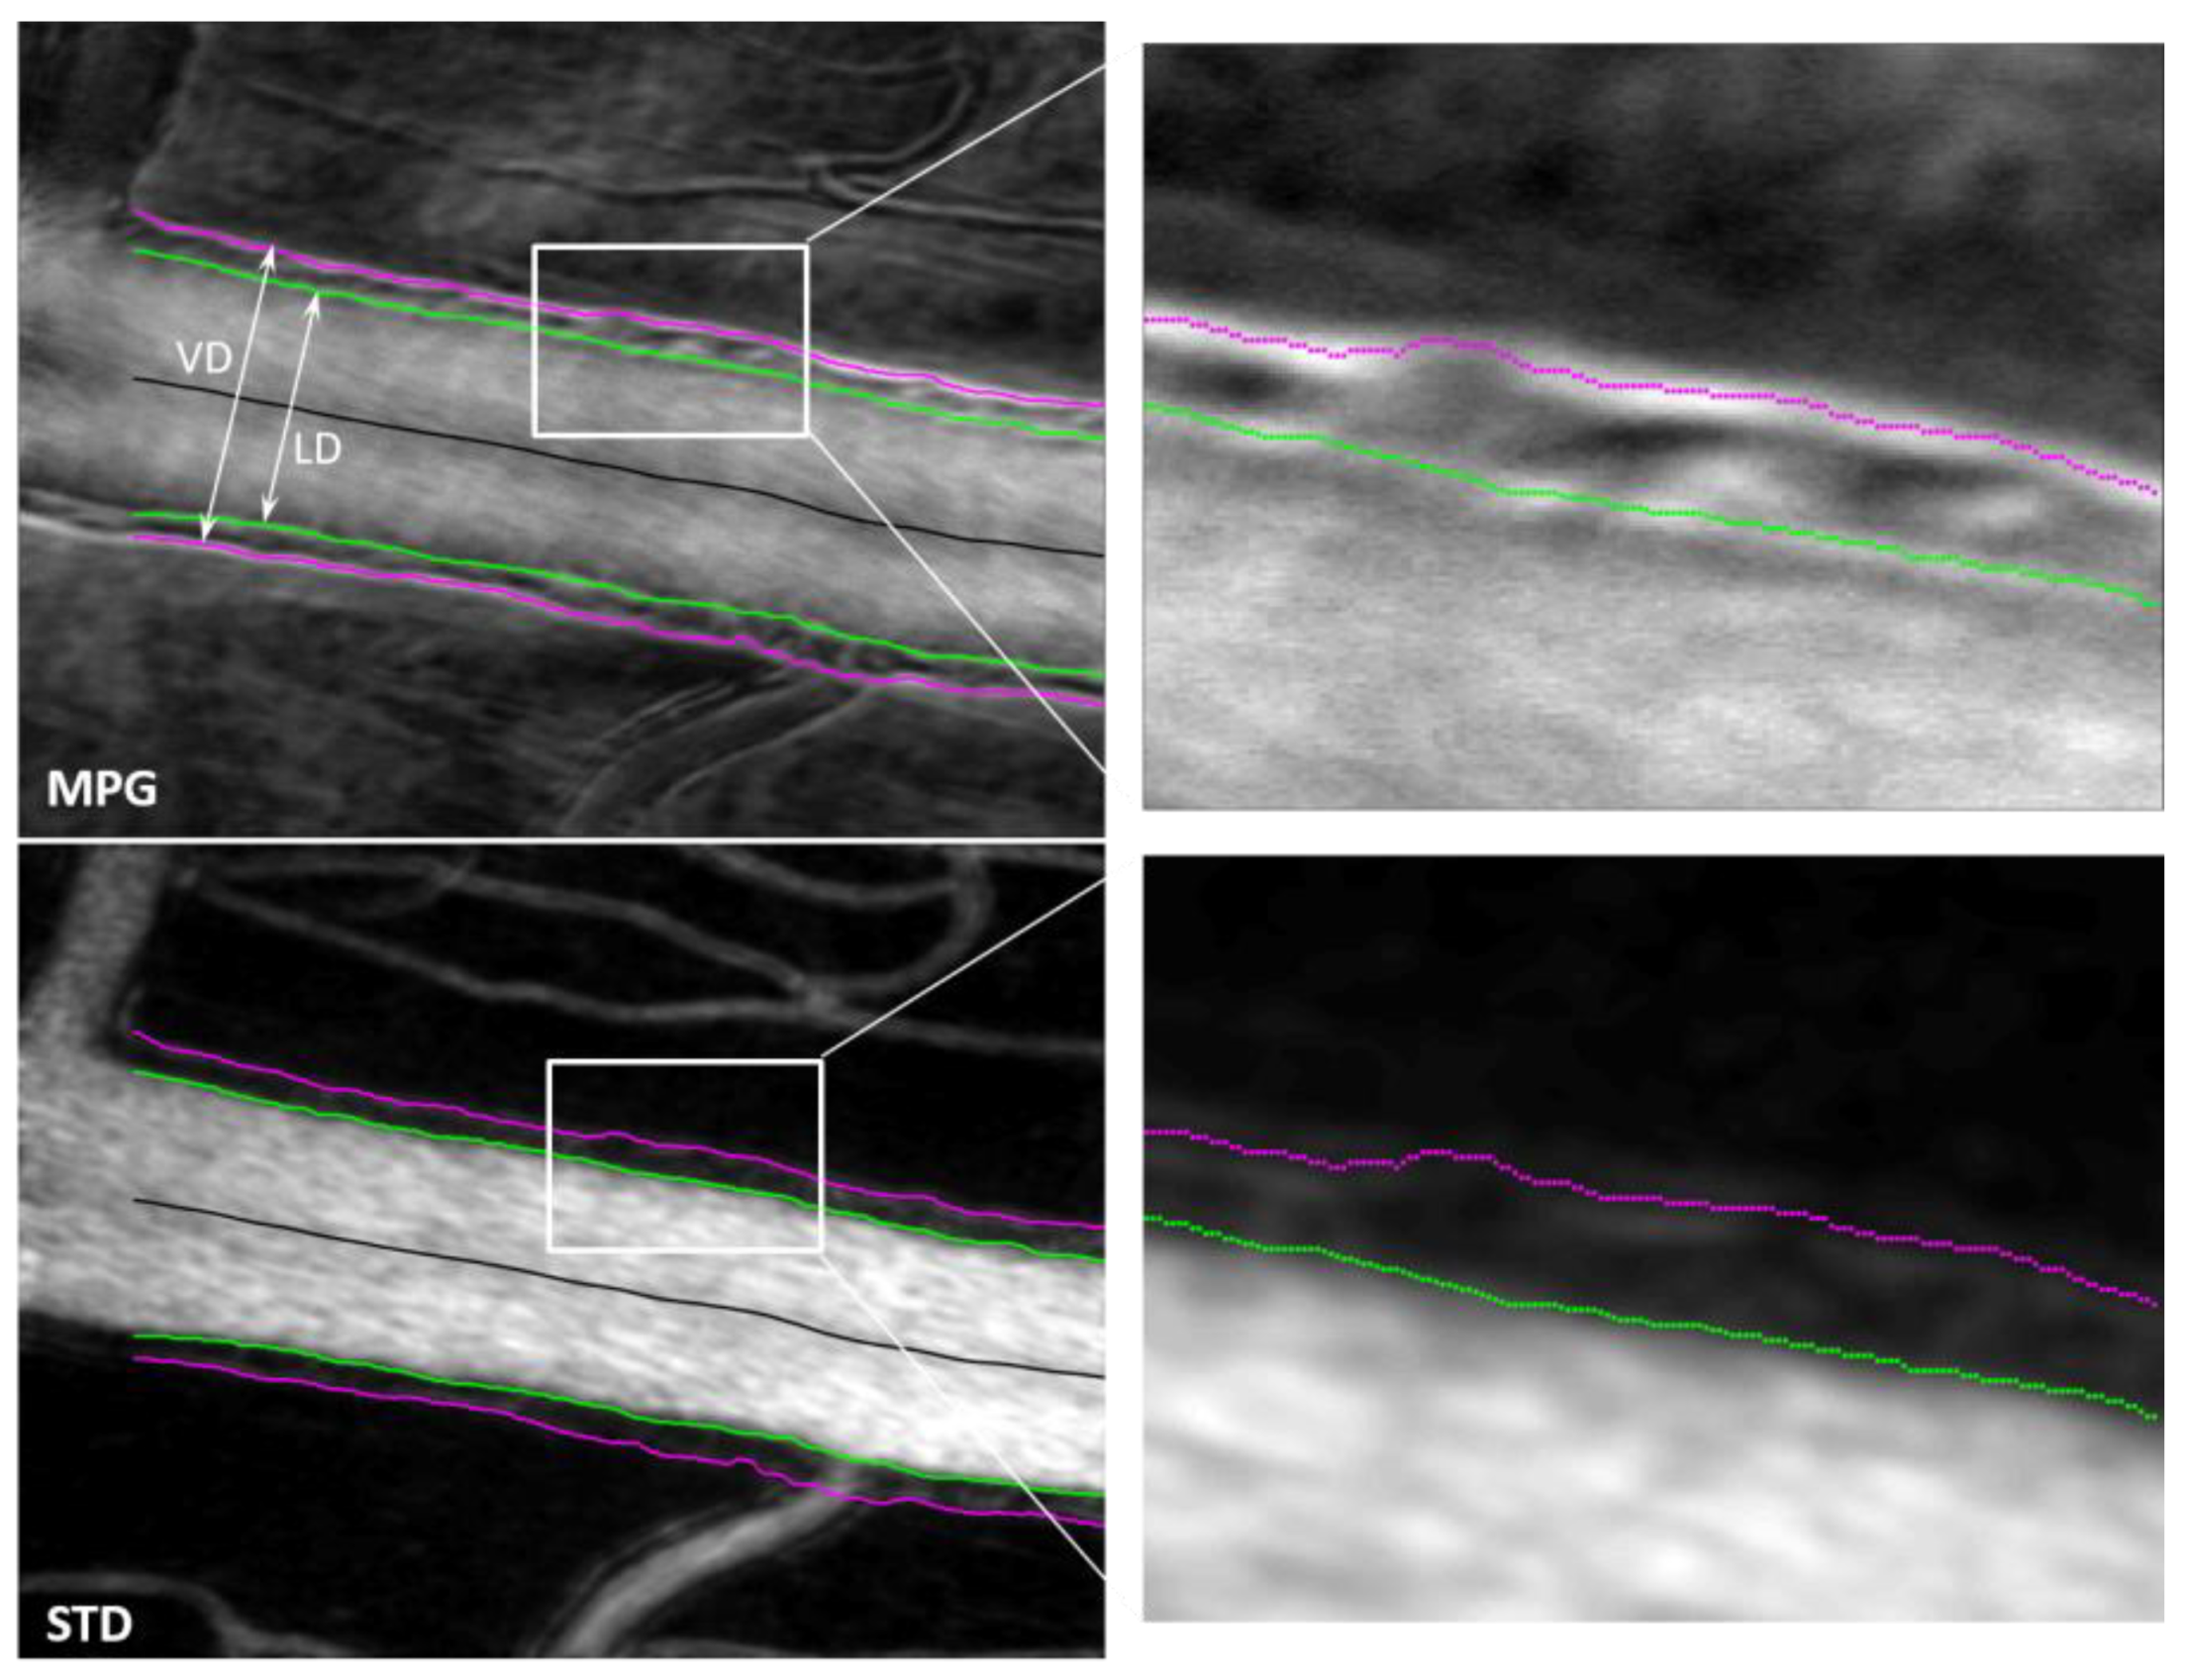

2. Materials and Methods

2.3. Confocal and Non-Confocal Imaging

3. Results

4. Discussion